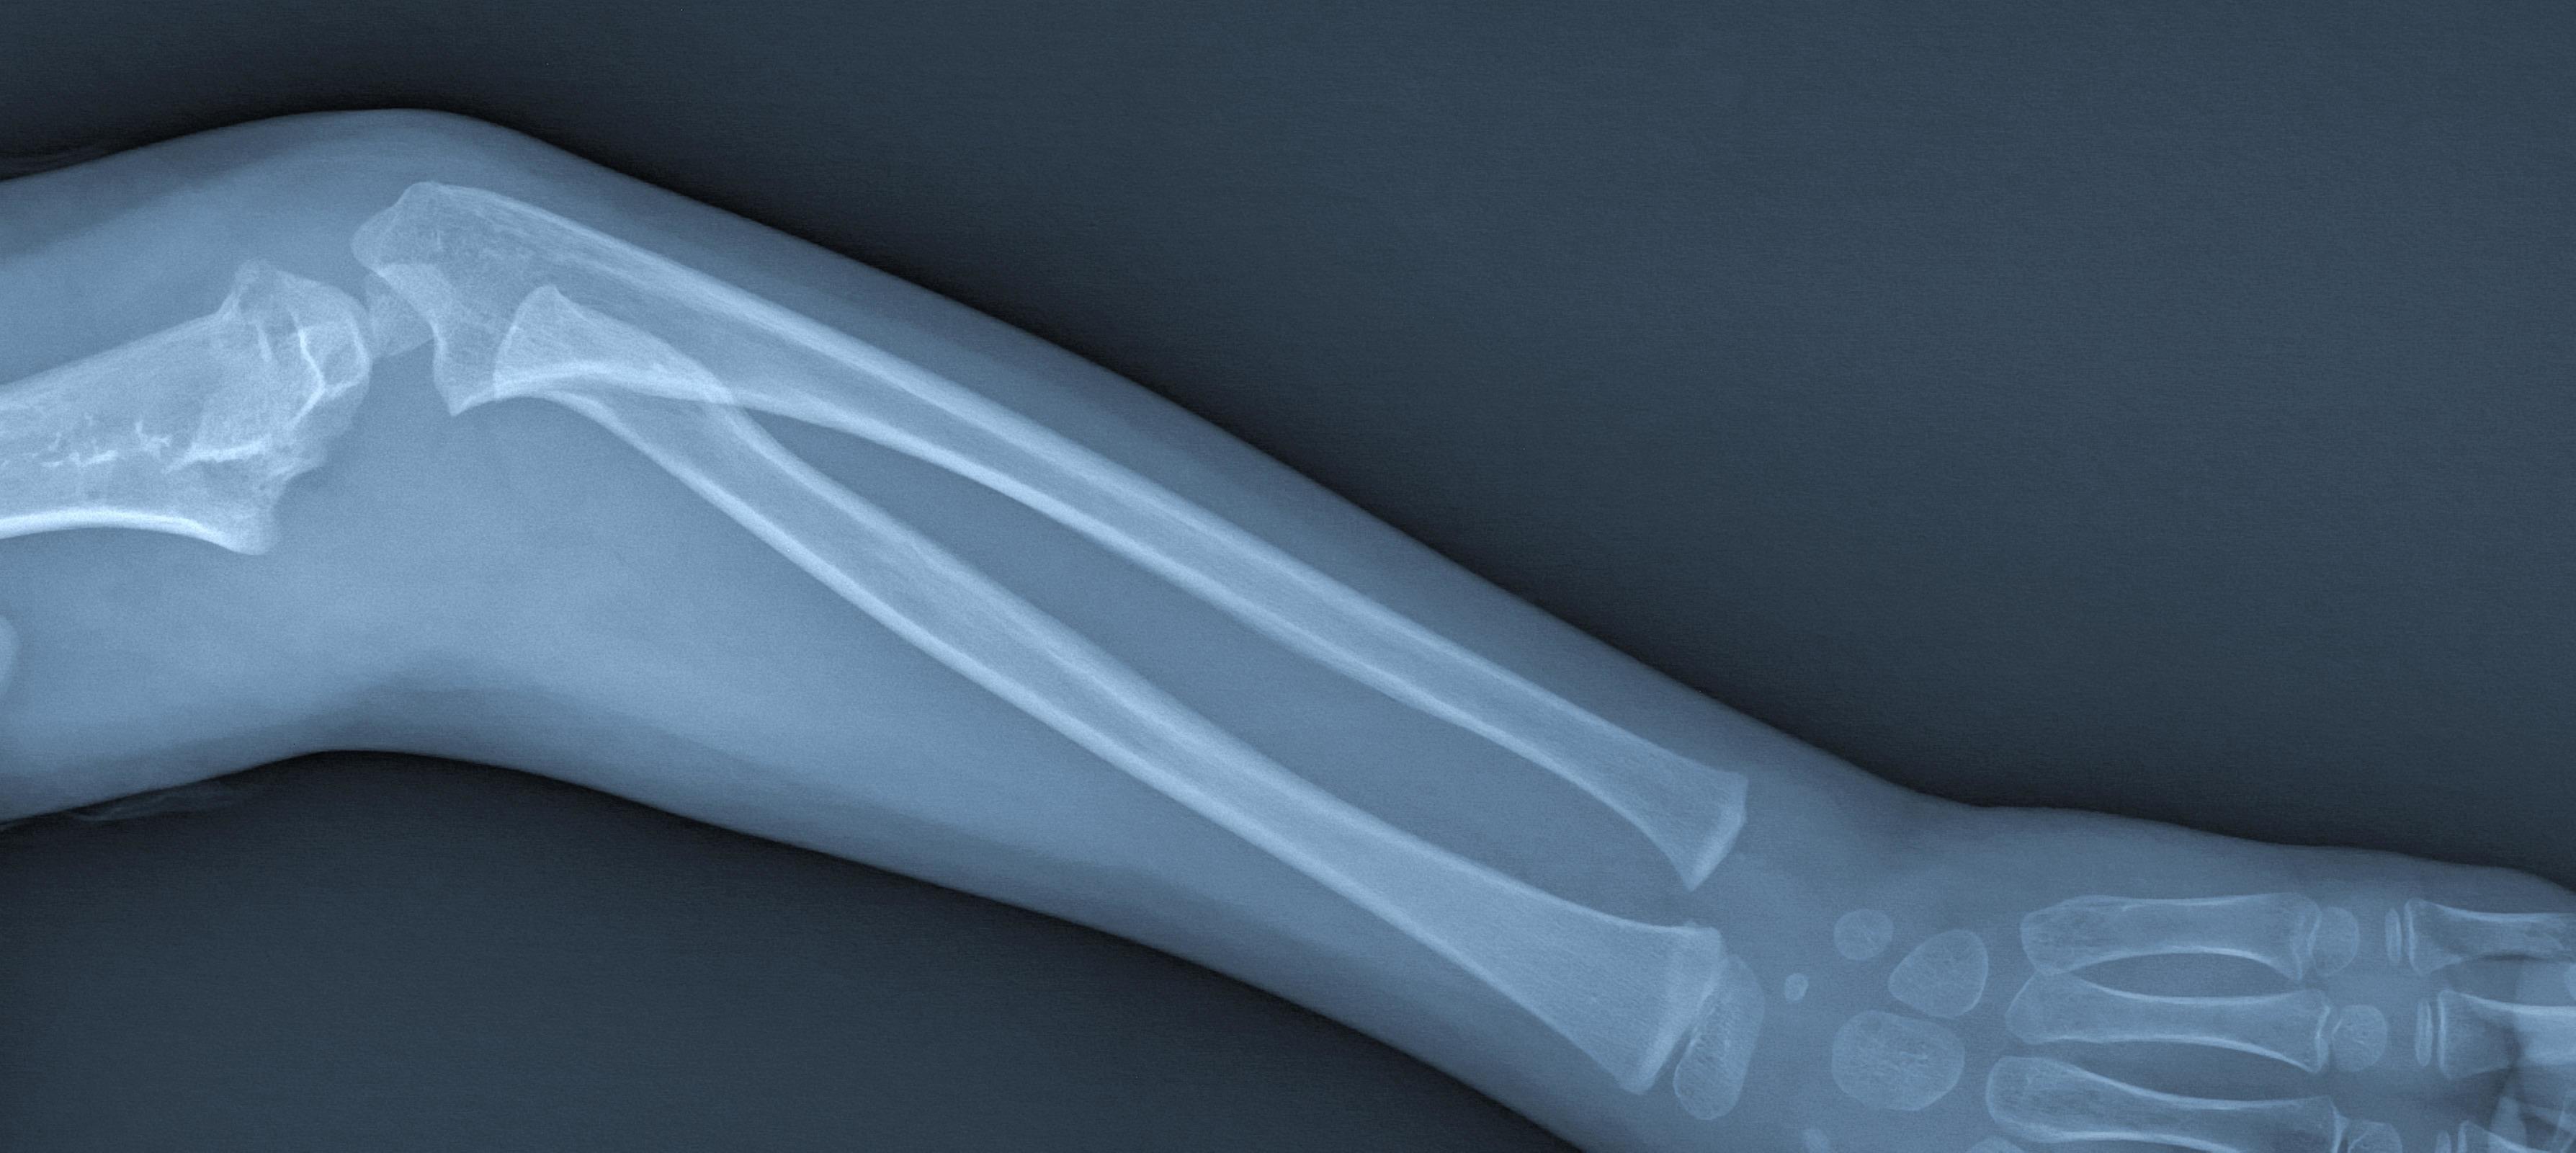

A Broken Arm X-Ray . Initially, most broken bones will have. It’s more common to break one of the two bones in. The doctor may examine your shoulder, upper arm, elbow, wrist, and hand, even if you complain only of arm pain. They might place a splint or cast to keep your arm still and in a better position. They can also show how many pieces of broken bone there are. A broken arm happens when any of the three bones in your arm are fractured. At least 2 views of the arm are taken. Learn about types, treatments, symptoms, healing time, pain relief, and surgery. If bones poke through the skin, this is called an open. You may have broken your arm or wrist if you've injured it and it suddenly became: With a broken arm, one or more bones are cracked.

A Broken Arm X-Ray A broken arm happens when any of the three bones in your arm are fractured. They can also show how many pieces of broken bone there are. A broken arm happens when any of the three bones in your arm are fractured. Initially, most broken bones will have. It’s more common to break one of the two bones in. You may have broken your arm or wrist if you've injured it and it suddenly became: Learn about types, treatments, symptoms, healing time, pain relief, and surgery. With a broken arm, one or more bones are cracked. At least 2 views of the arm are taken. If bones poke through the skin, this is called an open. The doctor may examine your shoulder, upper arm, elbow, wrist, and hand, even if you complain only of arm pain. They might place a splint or cast to keep your arm still and in a better position.